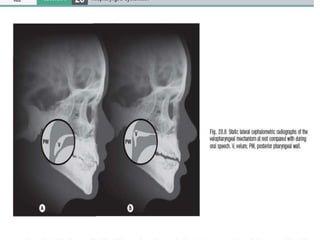

The normal point of contact

with the posterior pharyngeal

wall is located approximately

three-quarters of the way

back on the velum from the

posterior nasal spine (Fig.

28.3).

The site of velopharyngeal

closure is usually at or just

inferior to the palatal plane,

which is typically at or above

the level of the first cervical

vertibrae.